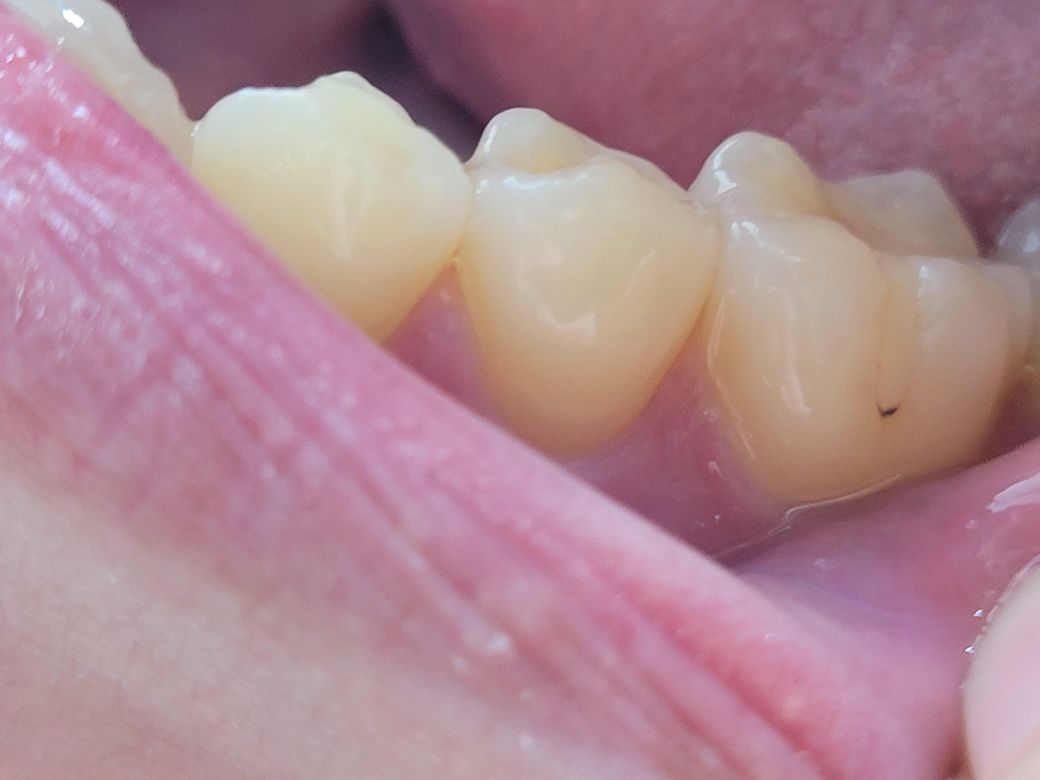

엑스레이는 한달이 지난 거여서 방금 찍은 치아사진도 첨부합니다

• 2번 째 사진